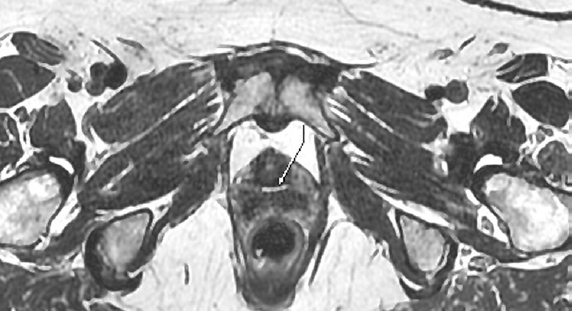

При оценке МРТ через 12 мес. структура аллогенного материала становится однородной (рис. 6), что свидетельствует о замещении его нативной тканью.

Рис. 6. Магнитно-резонансная томограмма органов малого таза через 12 мес. после операции.

Данные признаки указывают на успешное приживление аллотрансплантата и его функциональную адаптацию. Эти изменения демонстрируют, что спустя 6 мес. после операции процессы ремоделирования и биологической трансформации аллогенного материала продолжаются, обеспечивая его стабильность и прочность. Полученные с помощью МРТ данные о структурно-функциональных изменениях коррелируют с функциональными результатами. Это выражалось в отсутствии случаев эрозии, сохранении физиологической подвижности уретры и достоверно высоких оценках качества жизни. Важно подчеркнуть, что процесс ремоделирования протекал стандартно у всех пациенток, без признаков аномального рубцевания или ишемии, что объективно свидетельствует о безопасности и воспроизводимости результатов применения комбинированного аллогенно-синтетического слинга.